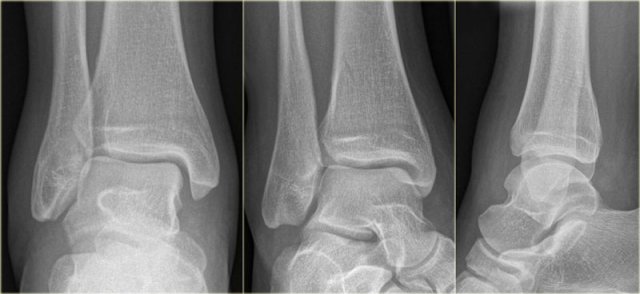

Triplane fracture Triplane fracture

At first this looks like a Weber B fracture with an oblique fracture in the fibula as seen on the lateral view (black arrows).

Notice however that this fracture line stops at the level of the epiphyseal plate.

So this is the fracture of the metaphysis in the coronal plane.

On the AP-view there is a lucency within the epiphysis, which is the epiphyseal fracture in the sagittal plane.

Notice also that the medial epiphysis is already closed, while the lateral portion is still open(blue arrows).

We have to assume that there is an epiphysiolysis of this lateral portion.

Here another example.

There is only a small metaphyseal fragment, which is usually the case (red arrow).

The fracture through the epiphysis is indicated by the blue arrow.